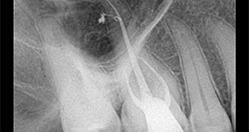

Dva dana ranije, u saobraćajnoj nezgodi, malu Marlenu udario je automobil. Na desnom gornjem centralnom sekutiću bila je prisutna fraktura gleđi i ...